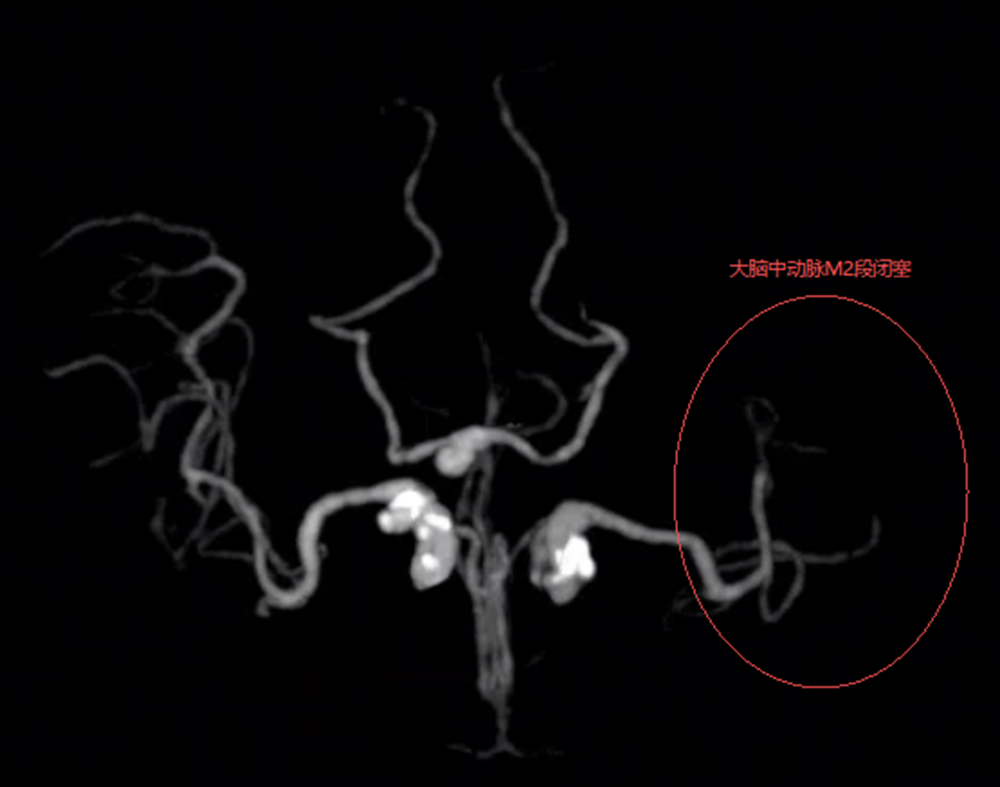

患者随即被送至CT室进行急诊多模式影像(CT血管成像)+CTP(CT灌注成像)检查,CTA+CTP检查提示:左侧大脑中动脉M2段闭塞;核心梗死区(已梗死的脑组织)范围较小,体积仅2.6ml,但缺血半暗带(缺血但仍可挽救的脑组织)体积高达178.2ml。不匹配比值高达69.5,属于显著的“大半暗带、小梗死核心”模式,意味着仍有大量脑细胞可以挽救!

头颈CTA提示左侧大脑中动脉M2段闭塞